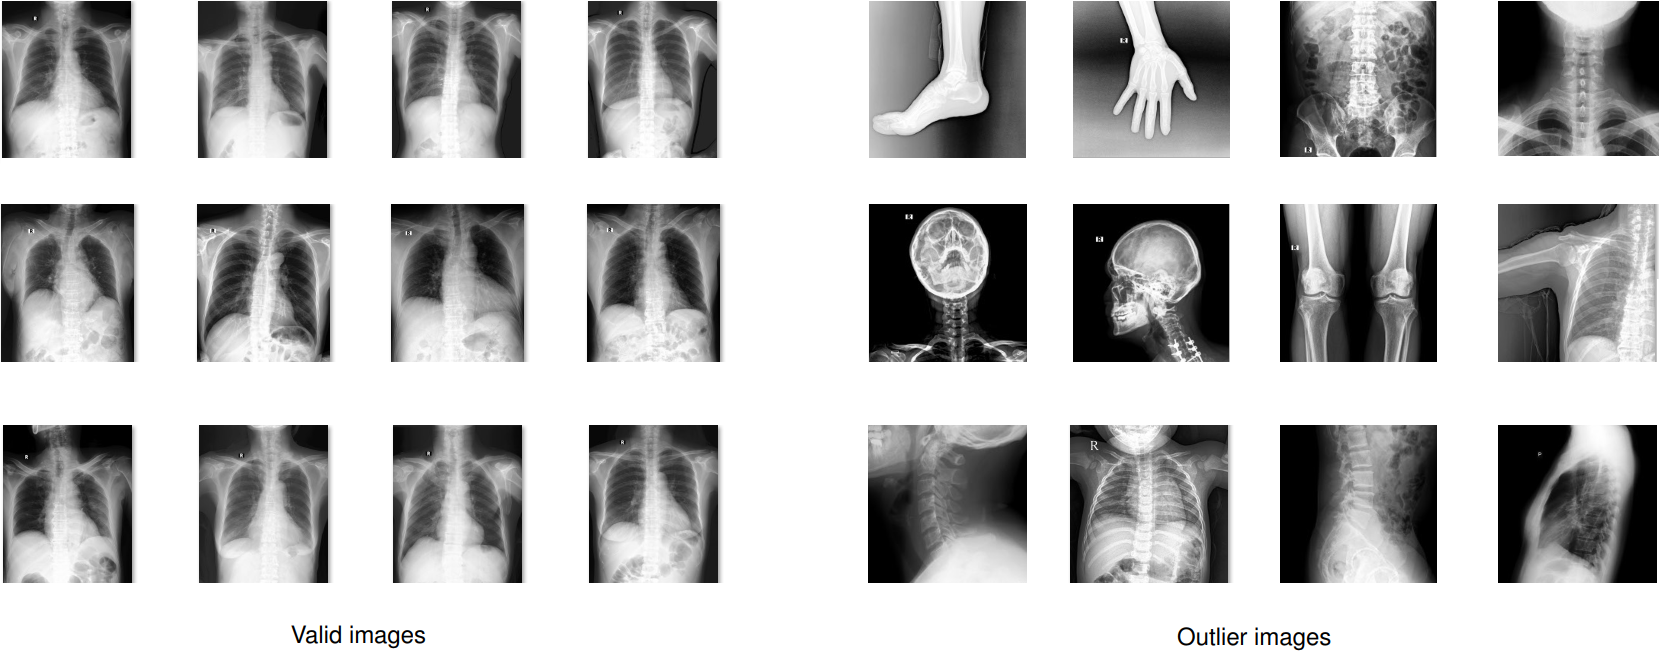

The collected raw data was mostly of adult PA-view CXRs, but also included a significant amount of outliers such as images of body parts other than chest (due to mismatched DICOM tags), pediatric scans, low-quality images, or lateral CXRs. Examples of these images are shown in Figure 2. All outliers were automatically excluded from the dataset using a binary classifier, which is a light-weight convolutional neural network (CNN). The training procedure of this classifier is out of the scope of this paper.